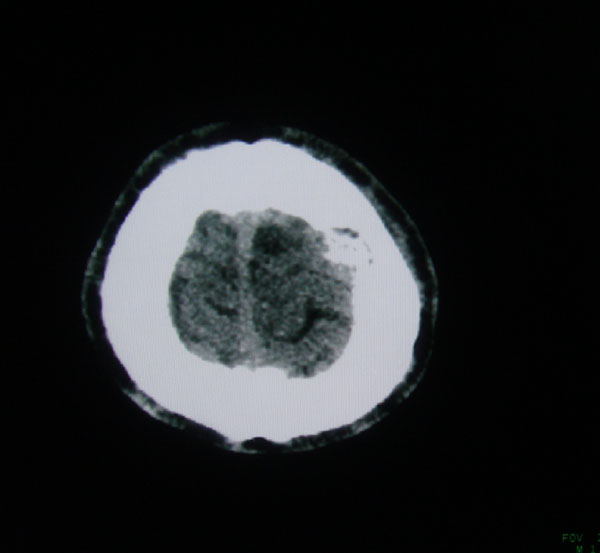

以下是引用zhangzhongshou在2008-6-7 12:49:00的发言:[br]左顶骨嗜酸性肉芽肿可能性大,建议ect及其他检查,除外转移瘤的可能。

以下是引用拾荒者在2008-6-7 13:05:00的发言:[br]左侧顶骨局限性骨质缺损,边缘锐利,无硬化边,周围软组织轻度肿胀,无明显软组织肿块及骨膜反应,考虑嗜酸性肉芽肿可能。